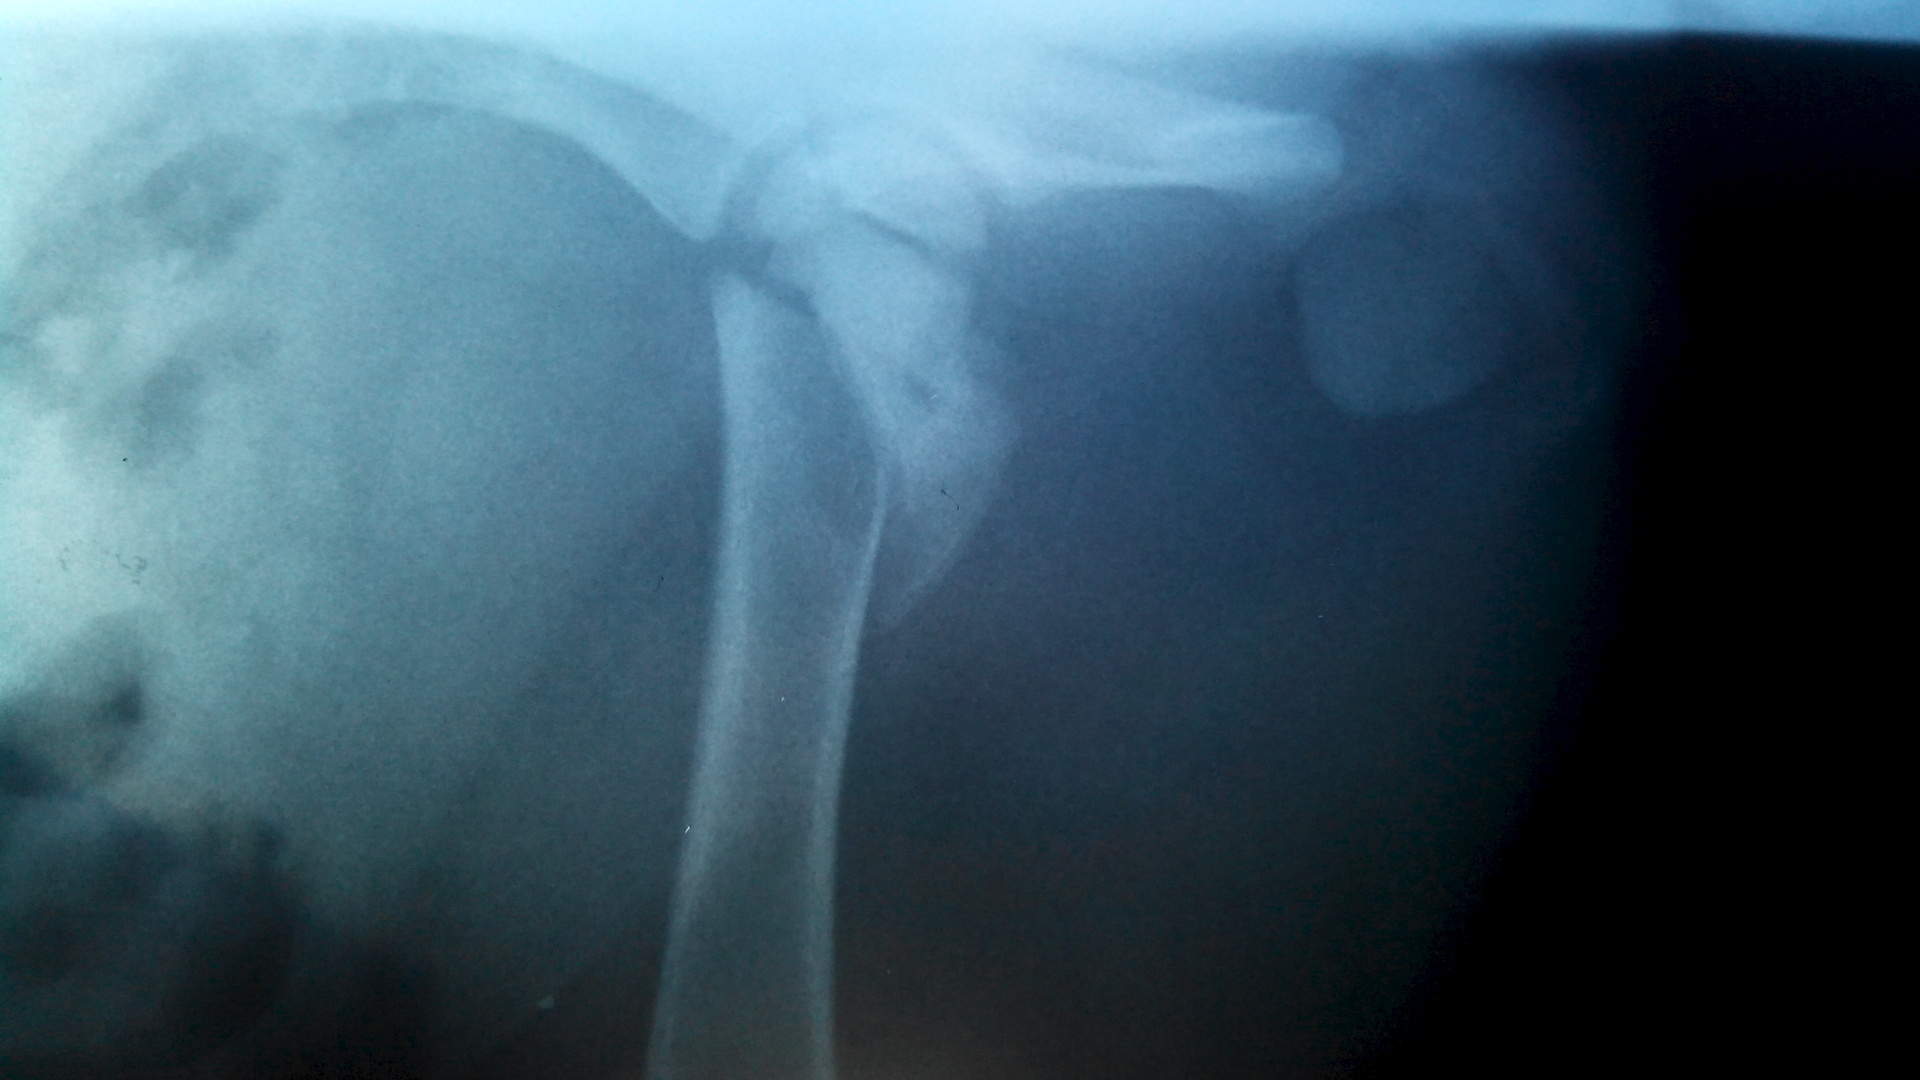

Здравствуйте. Ситуация: щенок 2 мес. лайка перелом левого тазобедренного сустава. Чрезвертельный перелом бедра со смещением кпереди на толщину кости и вверх на 1 см.